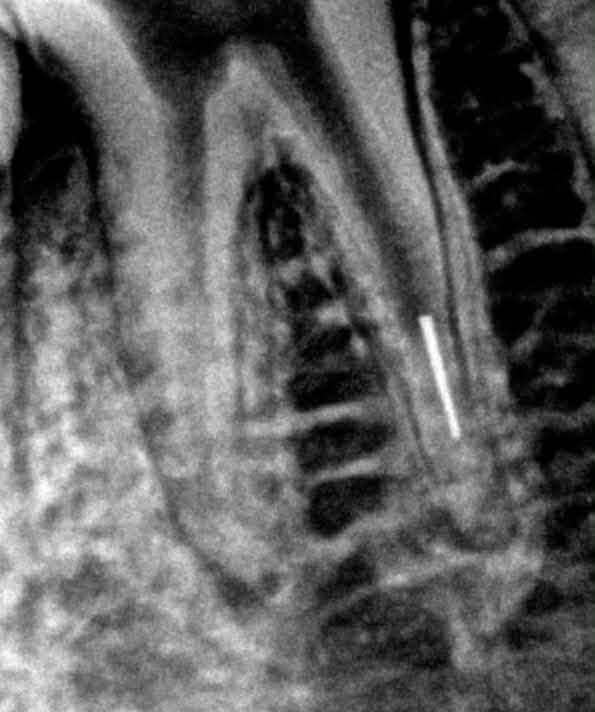

Quy Trình Lấy File Gãy Trong Điều Trị Nội Nha – Hướng Dẫn Chi Tiết Cho Bác Sĩ 1. Gãy file trong nội nha là gì? Gãy file nội nha là biến chứng thường gặp trong quá trình tạo hình ống tủy, đặc biệt ở các răng có ống tủy cong, hẹp hoặc vôi hóa. […]